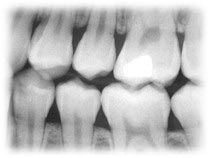

| קרני רנטגן וקרינה רדיו-אקטיבית קרניים חודרות האם עשו לכם פעם צילום שיניים? אם כן, בוודאי שמתם לב שלפני הצילום הניחו על החזה שלכם מעין "סינר" כבד. תפקידו של "סינר" זה הוא להגן על הגוף שלכם מפני ההשפעות המזיקות של קרינת הרנטגן (קרני איקס), שמכשיר הצילום פולט. האנרגיה של קרני הרנטגן גבוהה מאוד, ולכן הן חודרות בקלות מבעד לעור ולרקמות הרכות שבגופנו ומספקות לנו מידע חשוב על מצב השיניים והעצמות. ה"סינר" מכסה חלקי גוף שאין צורך לצלם, וכך הם מוגנים מפני הקרינה המזיקה. צילום רנטגן של השיניים בדומה לקרינת רנטגן, גם הקרינה הרדיו-אקטיבית היא קרינה מייננת, בעלת אנרגיה גבוהה, העלולה לגרום בגופנו לשינויים בחומר התורשתי שבתוך התאים ולהגביר את הסיכון להתפתחות של מחלות ממאירות. הקרינה הרדיו-אקטיבית נפלטת בתהליך ההתפרקות של חומרים מסוימים - חומרים רדיו-אקטיביים (כגון: אוראניום או רדון). גם לה יש שימושים חשובים ברפואה, בתעשייה ובמדע. הקרינה הרדיו-אקטיבית יכולה לפגוע בנו ישירות, דרך העור, אך אנו עלולים להיחשף אליה גם כשאנו שואפים אוויר (למשל: גז הרדון) או כשאנו בולעים מזון ומים המכילים חלקיקים רדיו-אקטיביים. חלקיקים אלה מתפרקים ופולטים קרינה רדיו-אקטיבית בתוך הגוף. סמל הקרינה הרדיו-אקטיבית כדי להפחית את הסכנות של חשיפה לקרני רנטגן ולקרינה רדיו-אקטיבית בשימוש רפואי, תעשייתי, או מדעי, עושים שלושה דברים: